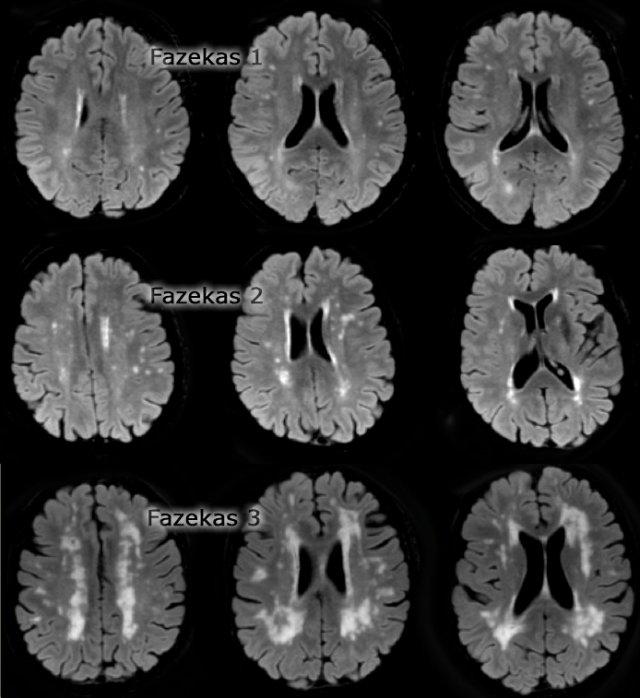

Thang điểm Fazekas đánh giá tổn thương chất trắng

Trên MRI, tăng tín hiệu chất trắng (WMH) và ổ khuyết – cả hai đều thường gặp ở người cao tuổi – thường được xem là bằng chứng của bệnh lý mạch máu nhỏ.

Thang điểm Fazekas cung cấp đánh giá tổng thể về sự hiện diện của WMH trên toàn bộ não.

Thang điểm này được đánh giá tốt nhất trên chuỗi xung FLAIR hoặc T2W mặt phẳng axial.

Điểm số:

- Fazekas 0: Không có hoặc chỉ có một tổn thương WMH dạng chấm đơn độc

- Fazekas 1: Nhiều tổn thương dạng chấm

- Fazekas 2: Bắt đầu hợp lưu các tổn thương (cầu nối)

- Fazekas 3: Tổn thương hợp lưu diện rộng

Thang điểm Fazekas đánh giá tổn thương chất trắng dự báo tình trạng tàn tật trong tương lai ở người cao tuổi.

Fazekas 1 được coi là bình thường ở người cao tuổi.

Fazekas 2 và 3 là bệnh lý, nhưng có thể gặp ở những cá nhân có chức năng bình thường.

Tuy nhiên, những đối tượng này có nguy cơ cao bị tàn tật.

Trong một nghiên cứu trên 600 người cao tuổi có chức năng bình thường, điểm Fazekas dự báo tình trạng tàn tật trong vòng một năm (bảng). Trong nhóm Fazekas 3, 25% bị tàn tật trong vòng một năm (10).

Theo dõi trong ba năm cho thấy các thay đổi chất trắng nặng một cách độc lập và mạnh mẽ dự báo sự suy giảm chức năng toàn thể nhanh chóng (17).